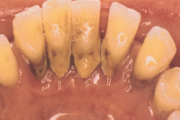

- igemed veritsevad (19)

- igemed punetavad (21)

- ige on paistes (mädapunn)

- igemed on tursunud/vohavad (17)

- puudulik suuhügieen (5)

- igemepealne hambakivi (5)

- igemealune hambakivi (4)